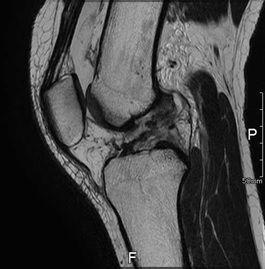

MRI所見

| 手術前 | 手術後 |

| ACLの緊張および連続性は消失している | 再建靱帯の成熟を認める |